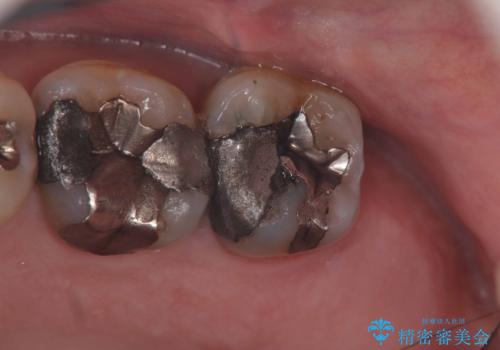

- 当院で治療後、メインテナンスに通っていただいている患者様です。

メインテナンスに通っていただきながら虫歯の治療や銀歯を外してフルジルコニアクラウンに変えています。

今回も不適合な銀歯を外したらその下は虫歯になっていました。